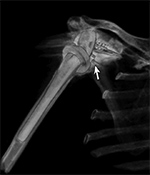

Variable Hardware Attenuation. (A) CT scout image demonstrates heterogeneous density of glenoid components of reverse total shoulder arthroplasty. (B) Axial CT image shows metallic glenosphere (curved arrow) positioned appropriately on less dense metaglene (straight arrow)